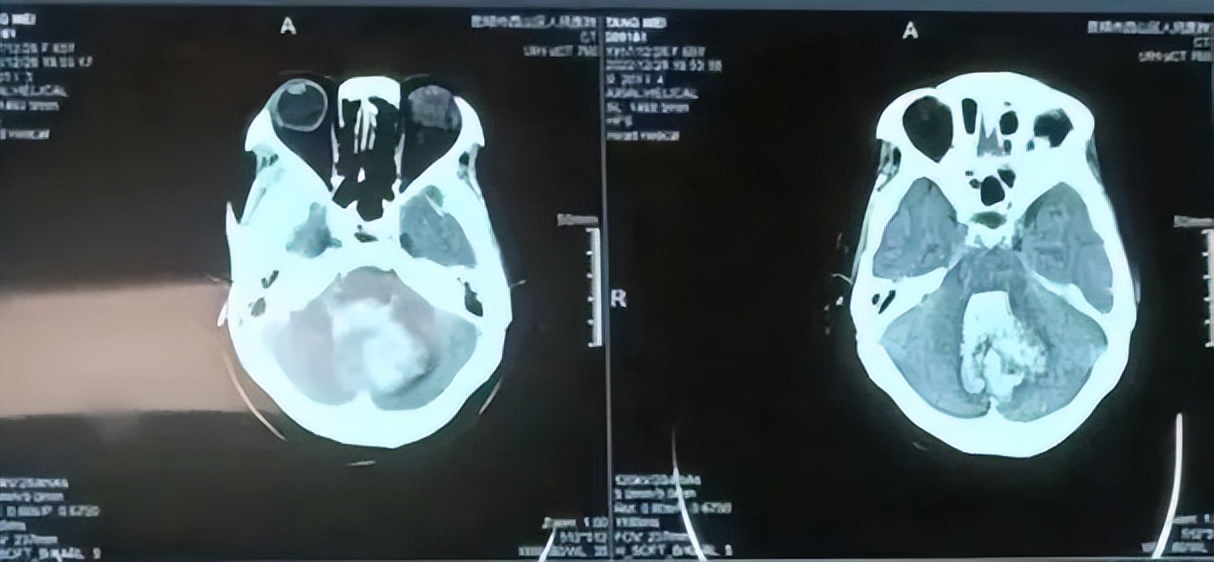

术前检查显示小脑出血破入脑室,挤压脑干

手术后血肿完全清除